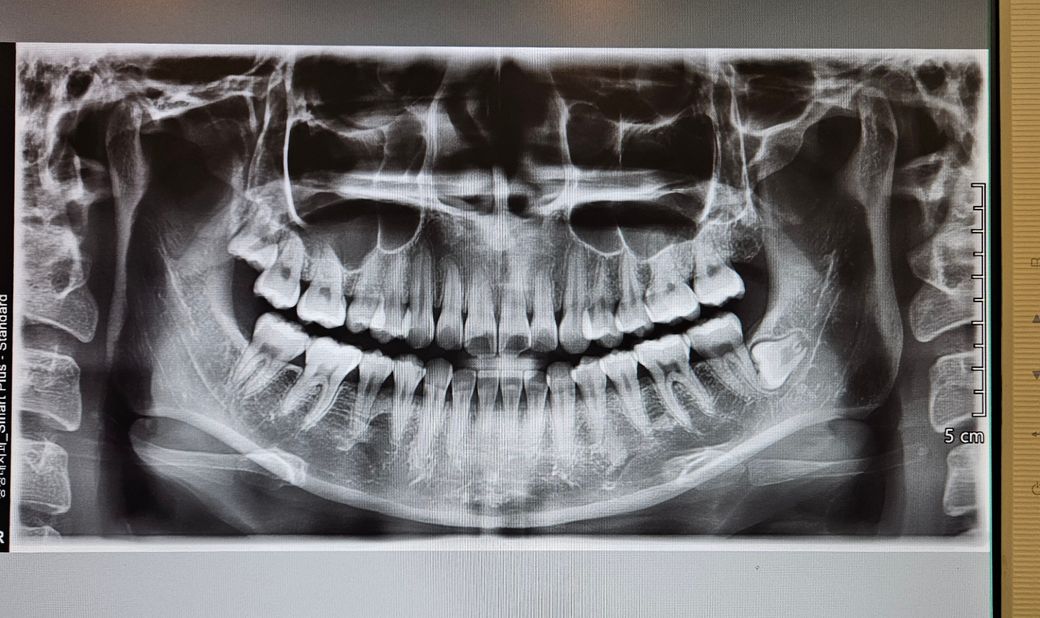

사랑니가 잇몸 안에 있는데 빼야하나요

사랑니가 잇몸 안에 있는 꼭 빼야하나요..? 병원 선생님께서는 안빼도 된다는데 진짜 안빼도 되나요? 인터넷에서는 다들 뺀다네요..

사랑니가 잇몸안에 완전히 박혀있을 경우에는 꼭 발치를 해야하는 것은 아닙니다.

주기적으로 검진 받으시고 문제 없으면 두시면 됩니다.

• 이 정도로 잇몸뼈에 묻혀 있는 경우는

별 다른 문제를 안 일으키는 경우가 많습니다.

특별히 불편한게 없으시다면 지켜보시는게 좋을 것 같습니다.

빼려고 하면 엄청 힘드실 겁니다.

• 안녕하세요 치과의사 김철진입니다. 왼쪽아래 사랑니는 별다른 이유가 없다면 발치를 하실이유는 없어 보입니다. 걱정하지 않으셔도 될것같습니다.

• 사랑니와 사진과 같이 잇몸 안에 완전히 들어가 있는 경우에는 큰 문제를 발생시키는 경우가 많지 않습니다. 따라서 발치를 해줄 필요는 없습니다. 그래서 주기적으로 사랑니가 정상적으로 위치하고 있는지를 치과에서 확인해주는 것이 좋습니다.

• 왼쪽 아래 사랑니를 말씀하시는 것 같습니다(사진상에선 오른쪽 아래) 해당 사랑니는 완전 매복 사랑니이며 신경관과 아주 근접하게 걸쳐있는 것으로 보입니다. 따라서 발치 전에 CT를 찍어 신경관과의 위치관계를 먼저 확인해야하며 발치 시 잇몸뼈를 일정량 쳐야합니다. 즉, 발치 시 득보다 실이 많기 때문에 특별한 이유(옆 어금니의 뿌리를 녹이고 있다던지, 교정 중 공간확보가 필요하다던지)가 없다면 굳이 발치를 권장드리진 않습니다.

• 매복 사랑니는 방향이 비뚤어져 나오면서 바로 앞 어금니에 걸리는 경우가 대부분입니다. 현재 사진상의 치아도 누워있어

그냥 두면 바로 앞 어금니를 상하게 할 가능성이 높기에 발치를 하길 권합니다.